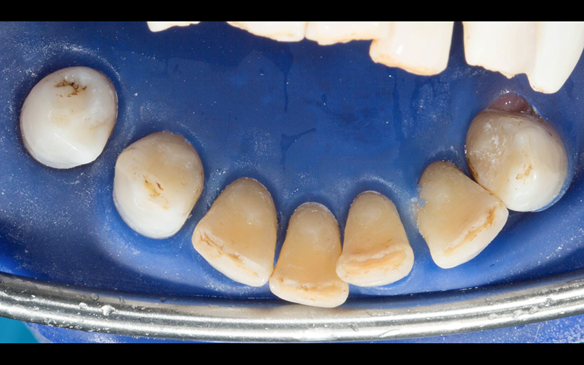

- Definitive dentures (Mk 2) – complete upper metal reinforced and lower cobalt chromium based partial of hygienic Scandinavian design to be made 9 - 12 months after extractions of all upper teeth and LR5 and LL4

The clinical situation and treatment process is shown in detail below with photographs.